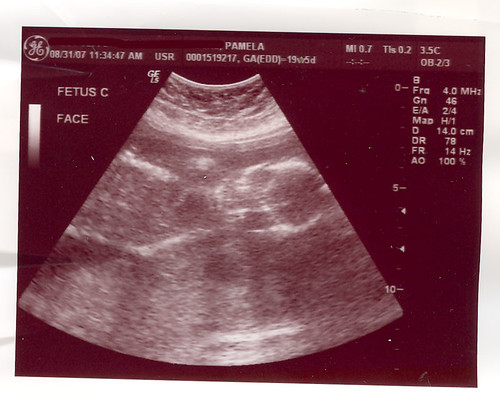

C: